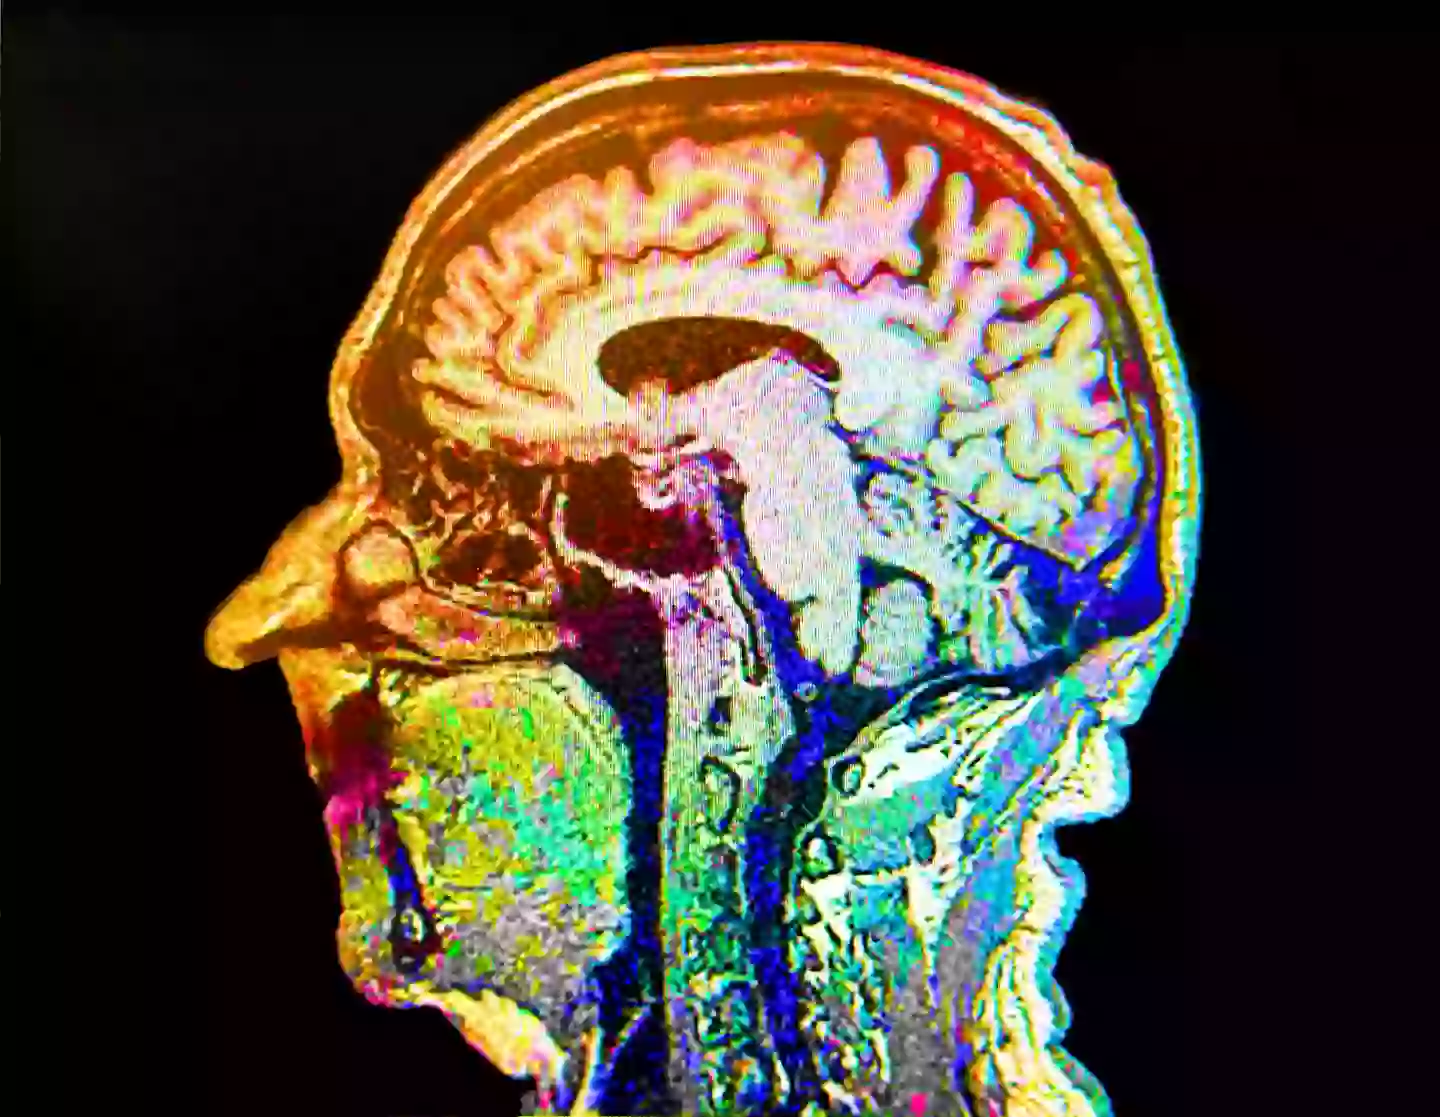

But this ‘brain scorecard’ tells you your risk of cancer, dementia and depression – morbid, I know. Created by scientists at the Harvard-affiliated teaching hospital Mass General Brigham in Boston, US, the new study is said to create a simple tool for individuals.

Described as being the first of its kind by Harvard Medical School lecturer in neurology Dr Andrew Budson, the ‘scorecard’ is designed to predict how your current habits may impact your brain health in the future.